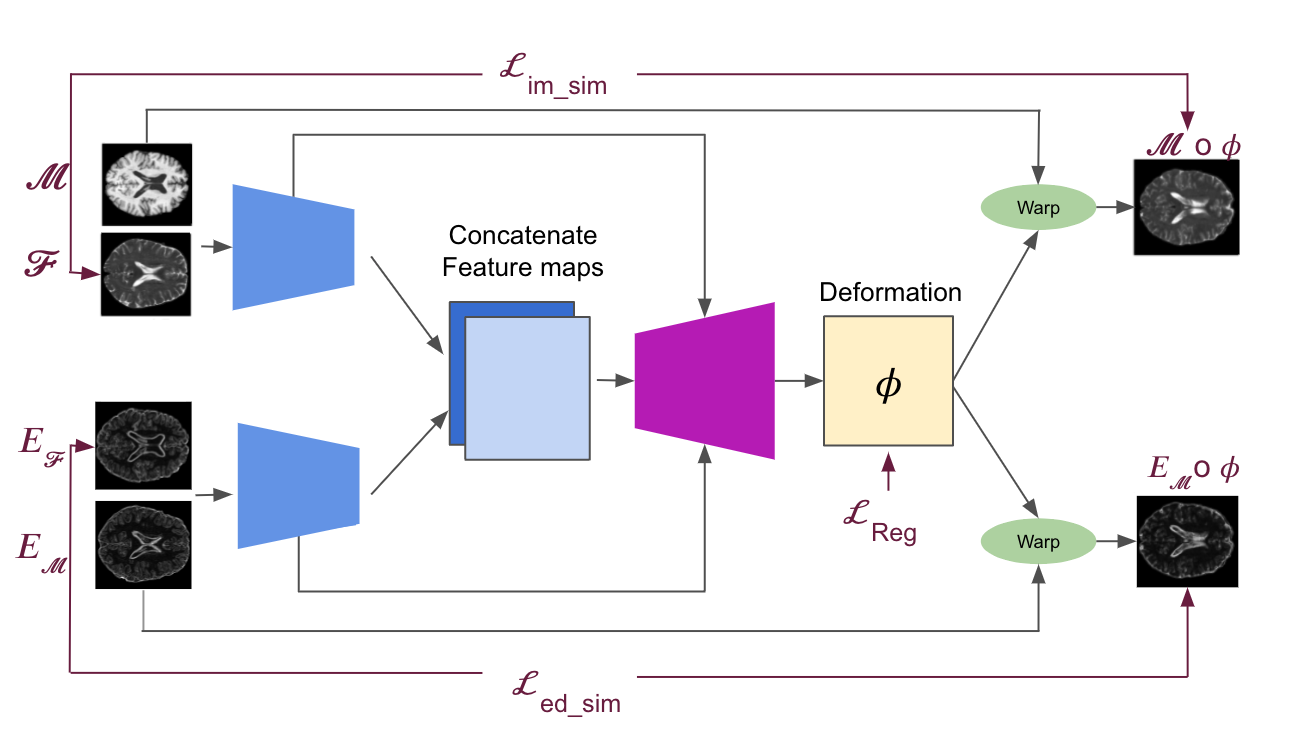

Different from the typical one-branch unsupervised image registration network, our approach leverages the deformation field estimated from two branches that perform image and edge registration simultaneously. This is very similar to the work of Zhe Xu at al. [12], but instead of trying to fuse the deformation fields resulting from the image and edge branches respectively, we try to estimate only one deformation field for both branches at the same time. The network architectures that we incorporated and extended are CNN networks based on Voxelmorph [3] and on MIDIR [6]. The whole pipeline of our method is depicted in 1. The network consists of 2 encoders: one for encoding the features of the images and the other for encoding the features of the edge maps. Then the encoded features are passed through a decoder that outputs directly a dense stationary velocity field (SVF), in the case of Voxelmorph, or the velocities of the B-spline control points from which we can compute the transformation via B-spline tensor product and Squaring and Scaling in the case of MIDIR.

In our effort to tackle the problem of multi-modal deformable image registration after the affine alignment, we decided to extend two different existing network architectures ([3] and [6]). The generic network architecture is depicted in Figure 1 and it is in general a convolutional U-Net [15] architecture that consists of two separate encoders without shared weights. The first encoder takes as input the T1w and T2w images, while the second one takes the edge maps of those. Both encoders reduce the spatial dimensions in half at each layer, operating on coarser representations. The features coming from the two encoders are then concatenated and passed to a common decoder which consists of upsampling, convolutions and concatenation of skip connections and outputs a dense velocity field or the B-spline control points. The velocity field can be a direct output of the network as described by [16], or can be determined using the B-spline control points from which the diffeomorphic transformation can be computed via B-spline tensor product and Squaring and Scaling, as described by [6]. All convolution layers use a kernel of size in all spatial dimensions and a stride of 2. The non-linearities are LeakyReLUs with a slope of .

During the training, the moving image and its corresponding edges are warped using the transformation via linear interpolation of the image intensities to generate the moving image and moving edge image respectively. These are then used to compute the image similarity loss and the edge similarity loss . The main goal is to find the optimal network parameters that minimise the loss function which is comprised by a term for image similarity, a term for edge image similarity and a term for the transformation regularisation on the velocity field.